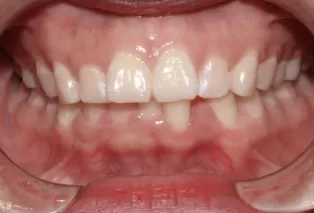

Female, 25 years old. Chief complaint: protruding and misaligned teeth, requiring orthodontic treatment.

Intraoral photos